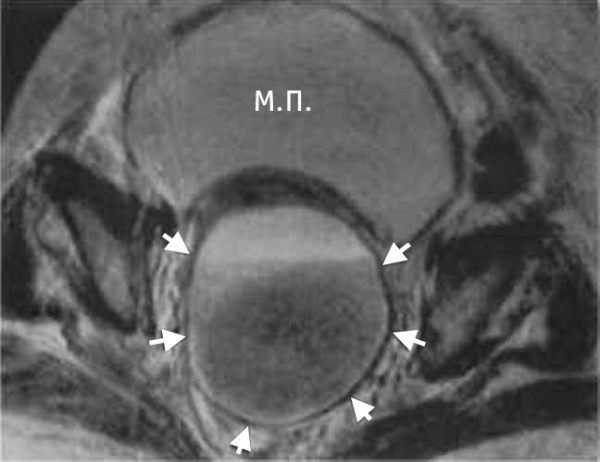

КТ органов малого таза. На снимке: абсцесс, отграниченный стенкой (А), прямая кишка (R), матка (U), мочевой пузырь (B)

Для дифференциальной диагностики с тубоовариальным абсцессом у женщин проводится УЗИ малого таза; для исключения абсцесса предстательной железы у мужчин – УЗИ простаты.

В сложно дифференцируемых случаях может потребоваться выполнение компьютерной томографии, МРТ. Для окончательного распознавания абсцесса дугласова пространства прибегают к диагностической пункции гнойника под ультразвуковым наведением через прямую кишку либо задний свод влагалища. Полученное гнойное содержимое подвергается бактериологическому исследованию.